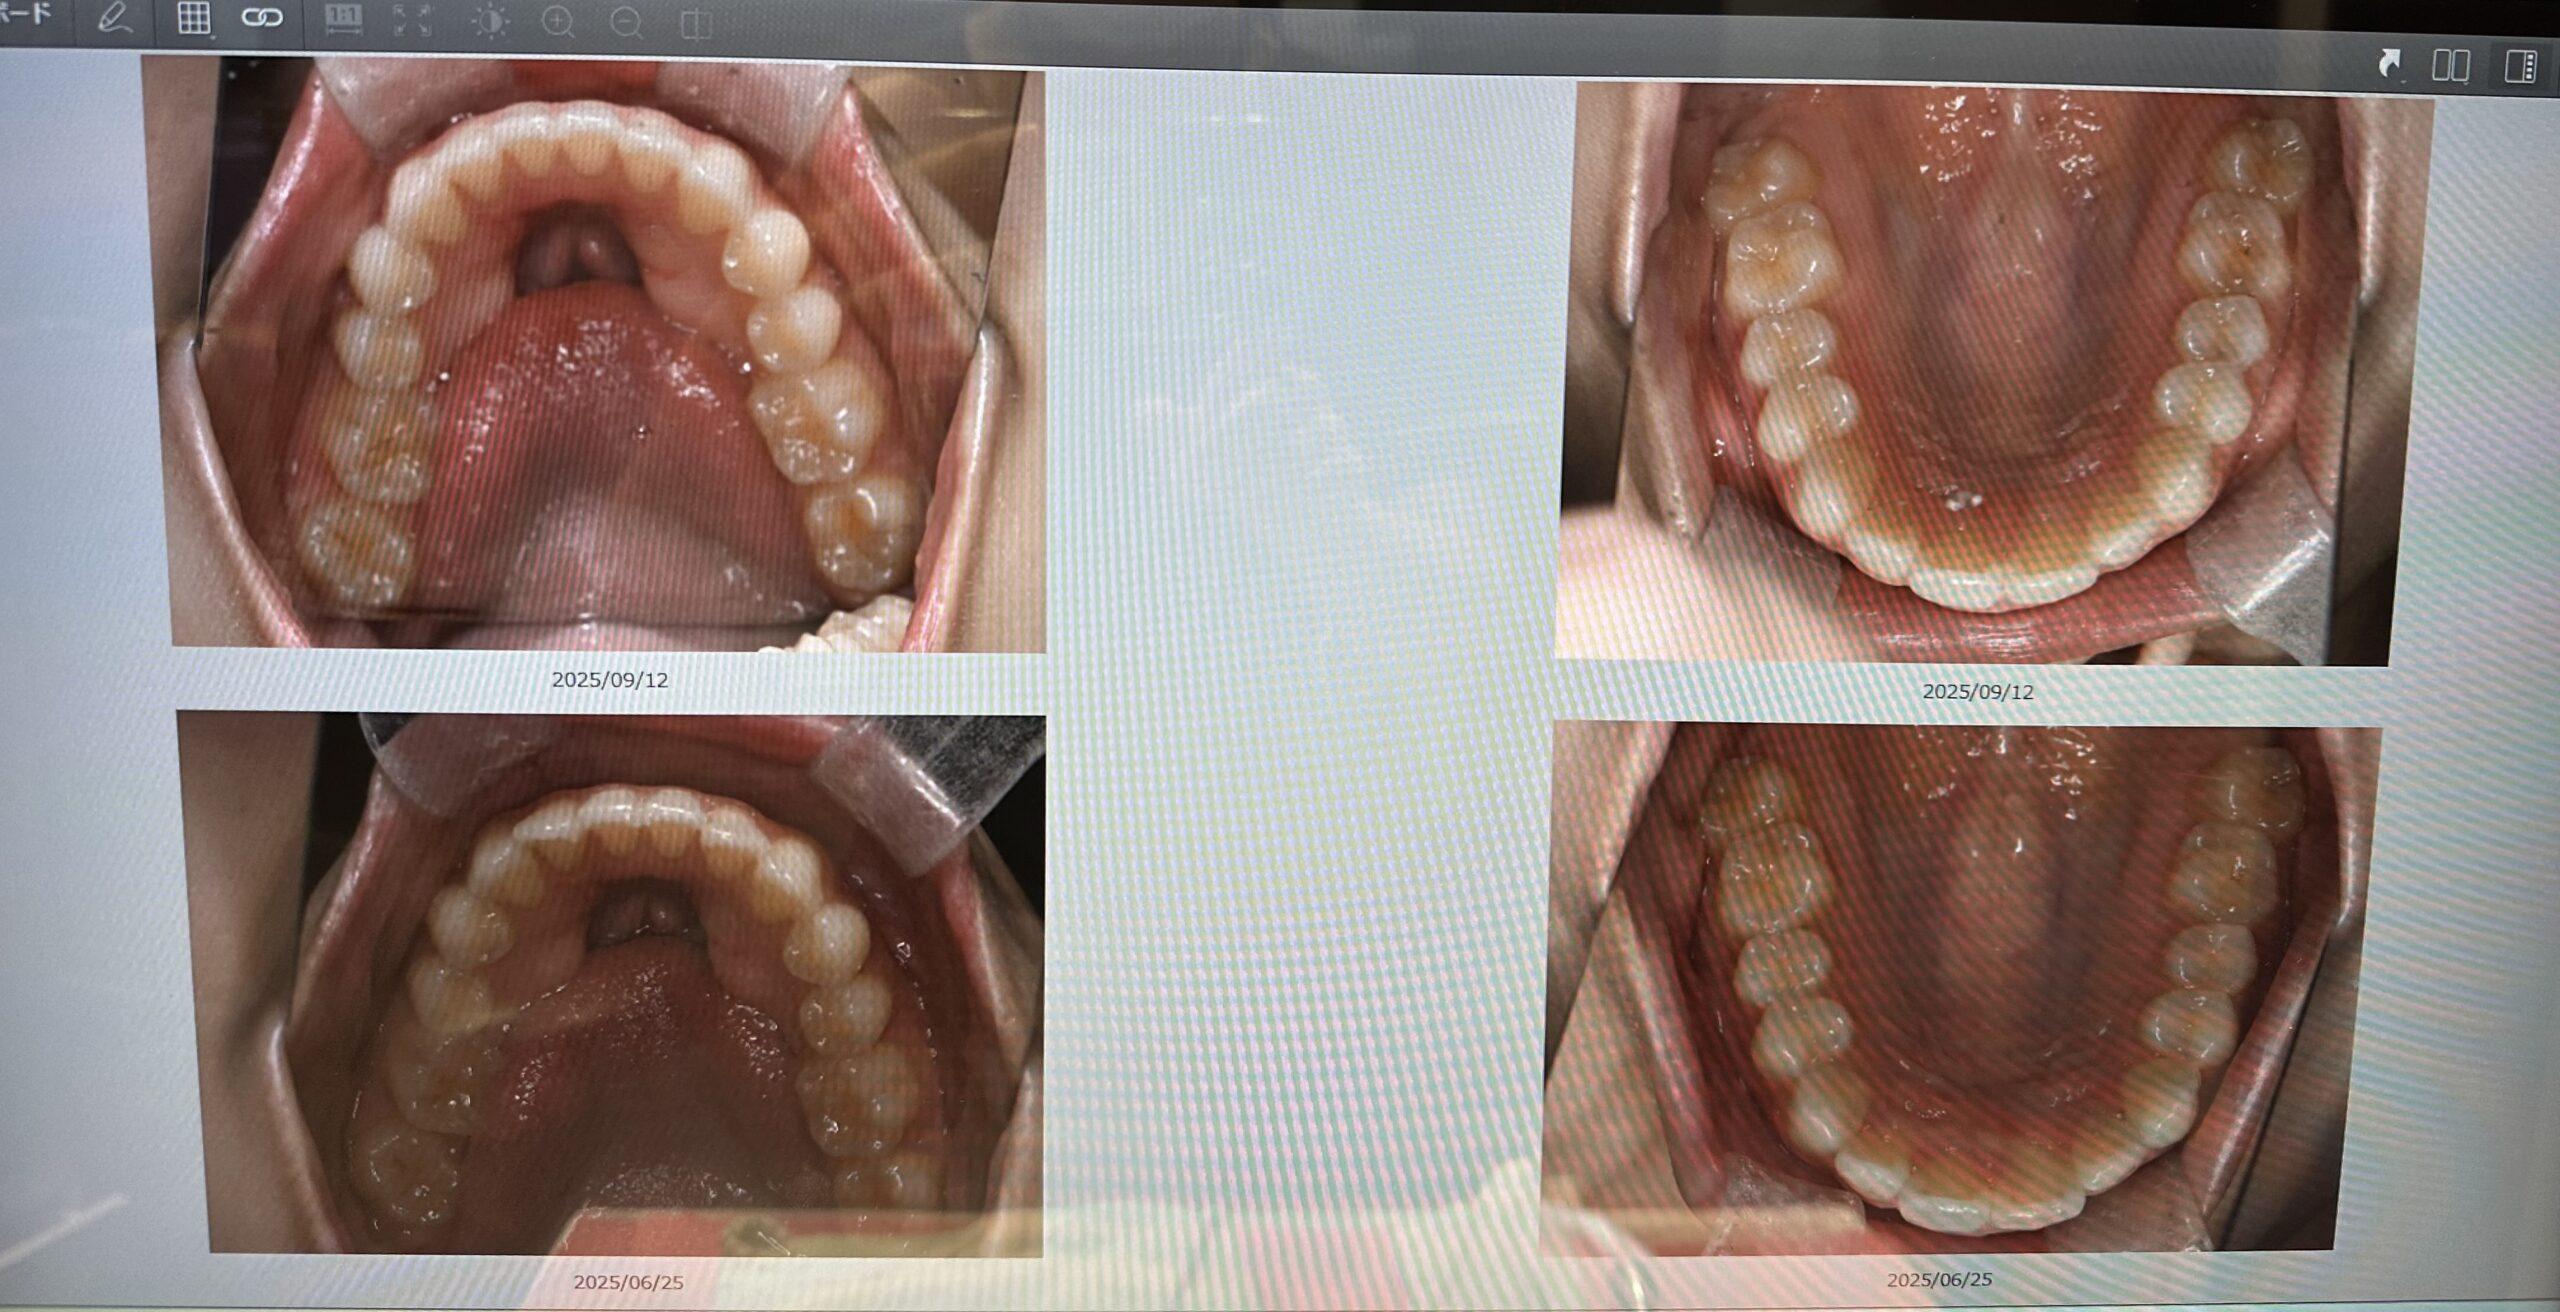

上の段が最新の写真で下の段が半年前の口腔内情報になります!

元々ワイヤー矯正をしていたので、そこまで歯並びは悪くないのですが、下の前歯のガタガタや上の前歯のでっぱりが綺麗に並んできました😆